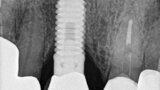

Fig. 13: The pre-op periapical radiograph revealed an existing implant-supported metal–ceramic restoration for the adjacent region #11.

Fig. 18: A periapical radiograph

with a drill in place confirmed that the apex length had been reached and that all the gutta-percha had been removed.